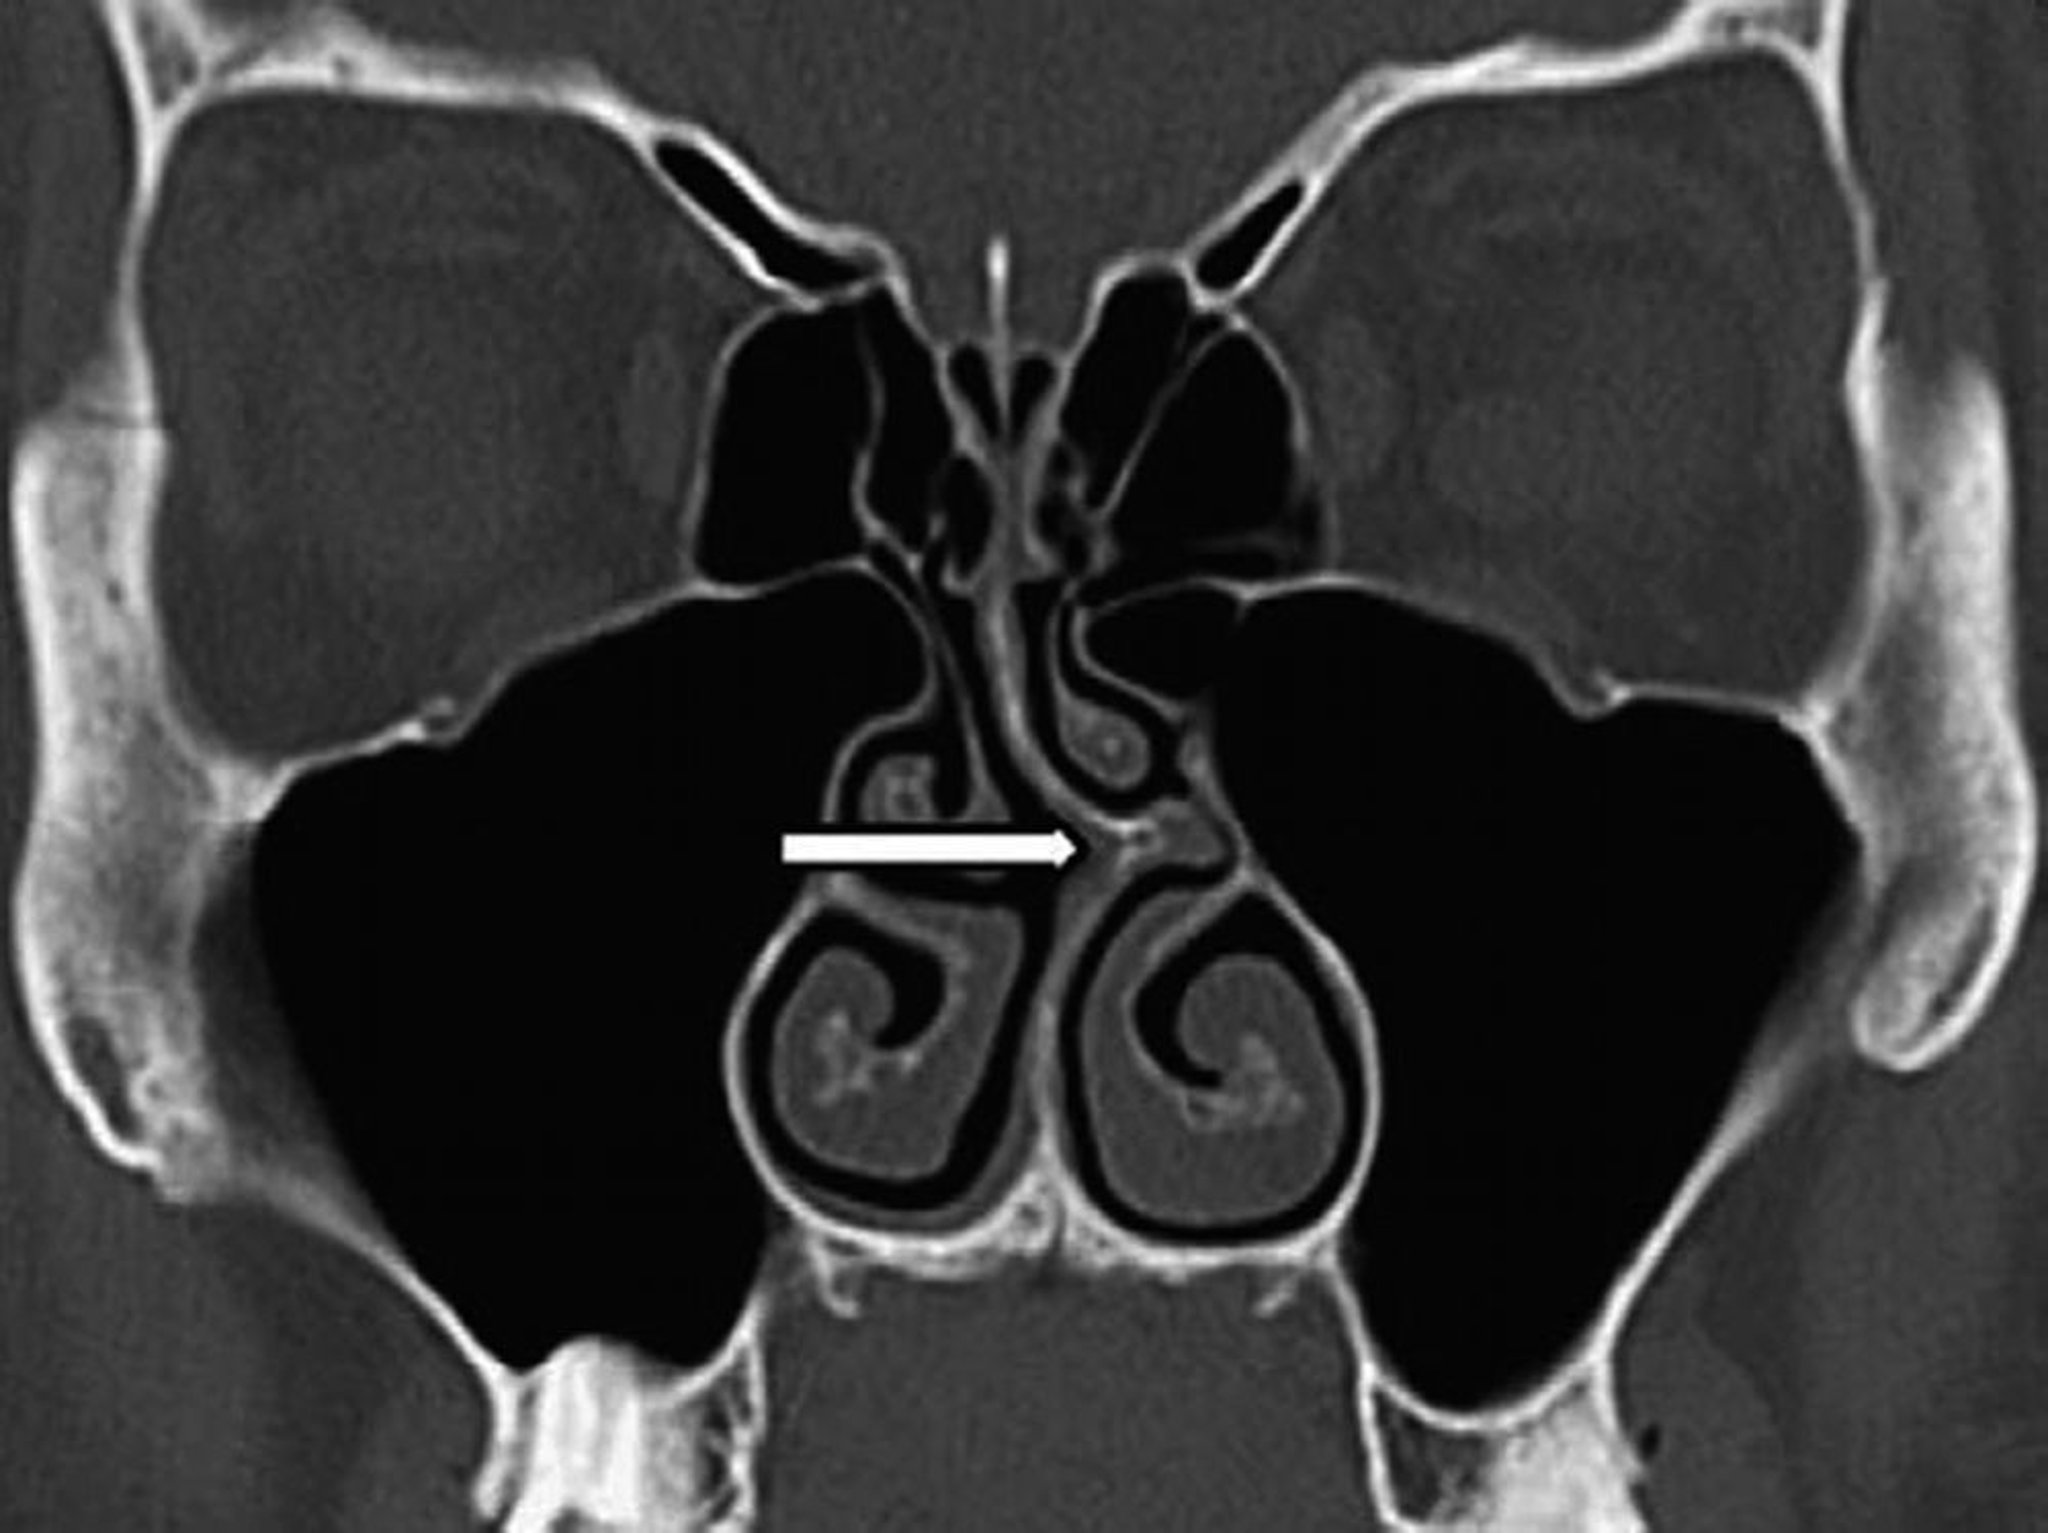

Deviazione settale (scansione TC)

Questa scansione TC coronale mostra la deviazione del setto nasale a sinistra (freccia).